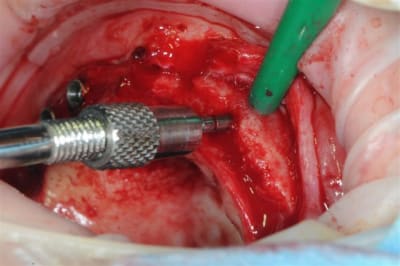

pas 40000, mais 2000 t/mn, ce qui n'est pas un bon plan pour les expanseurs meissinger, et à je crois bien provoqué un "m...e!" violent et la peur d'avoir tout explosé.

Mais non, mis à part une pénétration profonde (le spreader fait 15 mm pour une prévision d'implant de 10 mm)pas d'autres conséquence que des micros fractures crestale.

l'expansion en 22 à la jonction greffon os propre, faite à l'ostéotome manuel, malgré la non approbation de Thomas, c'est parfaitement passée, et nous avons constatés la parfaite liaison du bloc.

Mon truc c'est l'expansion, sous toutes ses formes,car je pense vraiment qu'il y a encore des progrès à faire.